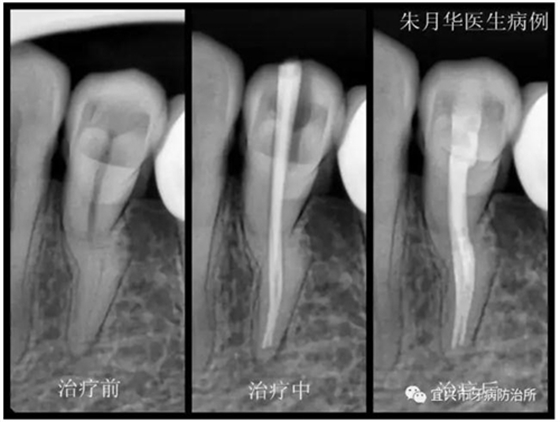

患者女,46歲,左下后牙疼痛不適數(shù)日余。經(jīng)檢查X線檢查,34根尖周牙周膜增寬,低密度影像,診斷為急性根尖周炎。處理:34局麻下開髓揭頂,測(cè)量根管長(zhǎng)度,10號(hào)C+銼預(yù)彎在EDTA潤(rùn)滑下疏通根管,疏通至20號(hào)K銼,隨后機(jī)用鎳鈦銼根管預(yù)備,疏通及根管預(yù)備期間次氯酸鈉不斷沖洗。封氫氧化鈣,ZOE暫封。一周后復(fù)診。去凈暫封物及根管內(nèi)封藥,隔濕,紙尖干燥,大錐度牙膠尖充填,隔濕,3M自酸蝕粘接劑+3M Z350光固化樹脂充填,調(diào)合,拋光。囑忌咬硬物,不適隨診。